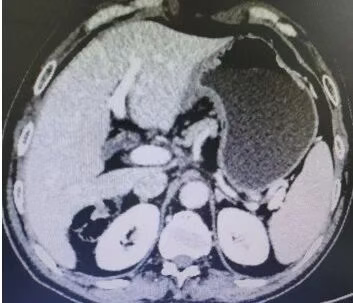

Abdominal CT films (2 sheets) on August 13, 2019